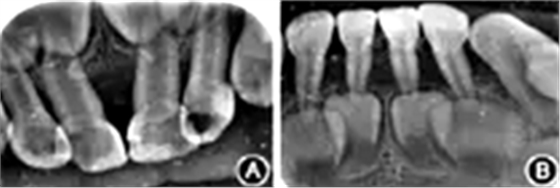

輔助檢查:基因檢測患者基因組ELANE基因有1個雜合突變(c.640G>A ),父母及其兄均未檢測到此突變,此突變?yōu)樽园l(fā)突變;血常規(guī):紅細(xì)胞3.13 × 1012/L,白細(xì)胞4.22 × 109/L,中性粒細(xì)胞絕對值0.48 × 109/L,血小板330×109/L,血紅蛋白83 g/L,C反應(yīng)蛋白>200 mg/L,超敏C反應(yīng)蛋白>5.0 mg/L??谇籜線片示牙槽骨呈廣泛性吸收達(dá)根中及牙尖1/3,遠(yuǎn)中切角缺損,牙冠可見低密度影像(圖2)。

圖2 重型先天性中性粒細(xì)胞缺乏癥患者前牙X線片示牙槽骨廣泛性吸收

A:上頜前牙;B:下頜前牙